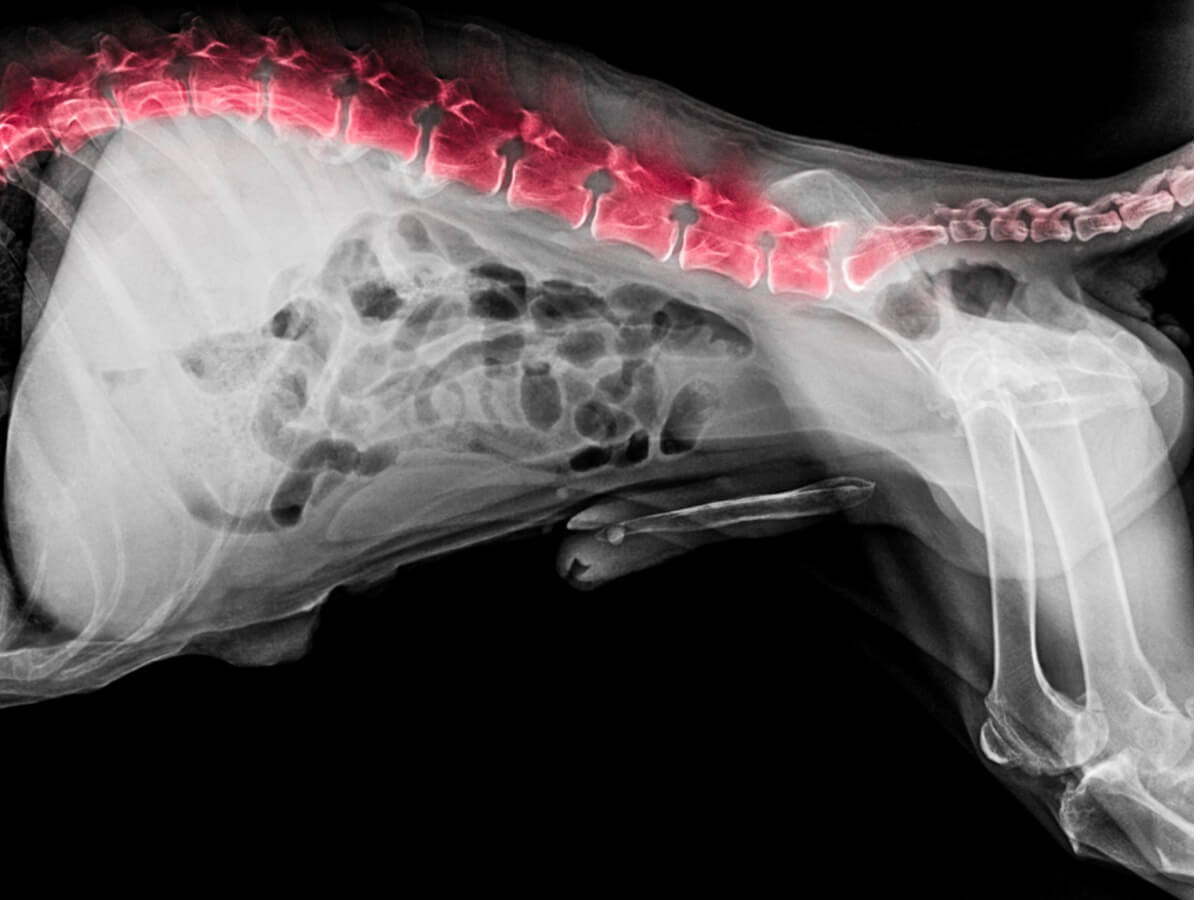

Tämän lisäksi tehdään radiologinen tutkimus (otetaan röntgenkuvat) nikamien kunnon selvittämiseksi. Röntgenkuvien avulla selvitetään, onko koiralla selkärankareumaa, välilevytyrää, välilevykulumia, infektioita, kasvaimia tai muita vaivoja.

Jos tulokset ovat edelleen epäselvät, tehdään tarkempi diagnostinen tutkimus magneettikuvauksella tai tietokonetomografialla. Näillä menetelmillä saadaan paljon tarkempia ja varmempia tuloksia kuin muilla edellä mainituilla lähestymistavoilla.